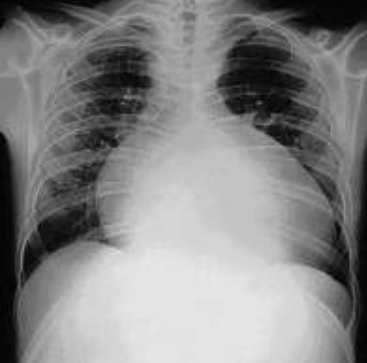

Lactente de 6 meses, previamente hígido, é levado à emergência pediátrica com quadro de tosse produtiva há 2 dias, associado com febre de 39 graus e dispneia. Ao exame físico: regular estado geral, descorado 1+, hidratado, acianótico, anictérico e afebril. FC = 180 bpm, FR = 65 ipm, SatO2 95% em ar ambiente. Murmúrio vesicular normodistribuído, com estertores subcrepitantes difusos, com tiragem subcostal moderada, 2 bulhas rítmicas hipofonéticas, sem sopros cardíacos. Pulsos periféricos cheios e TEC 4 segundos. Abdome com fígado palpável a 4 cm abaixo do rebordo costal direito. Restante sem alterações. Foi solicitado Rx tórax

(vide abaixo – fonte: Medscape®).

Assinale a alternativa que apresenta a principal hipótese diagnóstica.